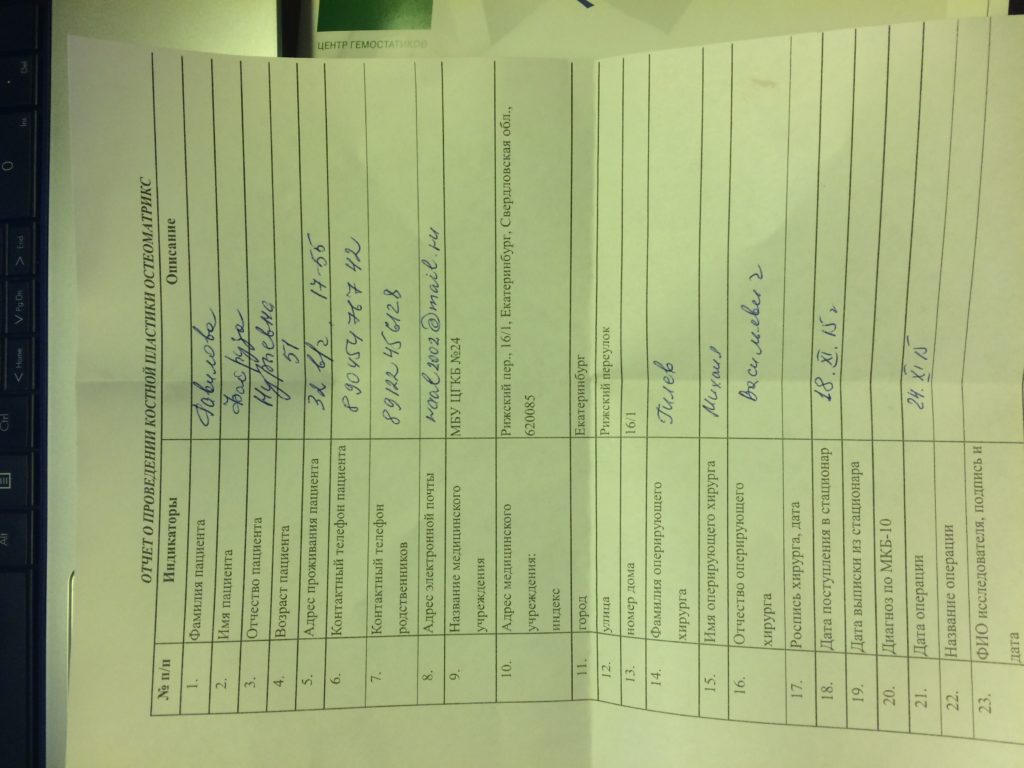

Операция - открытая репозиция, остеосинтез лучевой кости пластиной с костной ксенопластикой материалом "Остеоматрикс". На контрольных снимках в три месяца имеется консолидация перелома, миграции фиксатора нет, имеется остеоинтеграция ксенопластического материала.